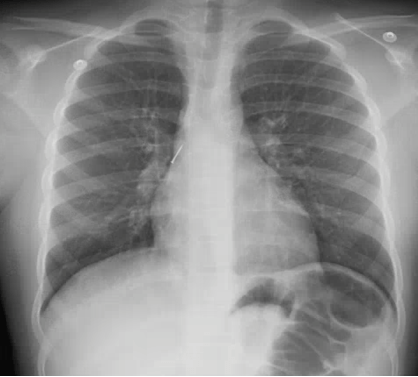

What’s the Diagnosis? Gepost op 29 april 2019 door netwerkvsseh What’s the Diagnosis? @emdaily.cooperhealth.org Dit delen: Delen op X (Opent in een nieuw venster) X Share op Facebook (Opent in een nieuw venster) Facebook Delen op LinkedIn (Opent in een nieuw venster) LinkedIn E-mail een link naar een vriend (Opent in een nieuw venster) E-mail Afdrukken (Opent in een nieuw venster) Print Vind-ik-leuk Aan het laden... Gerelateerd